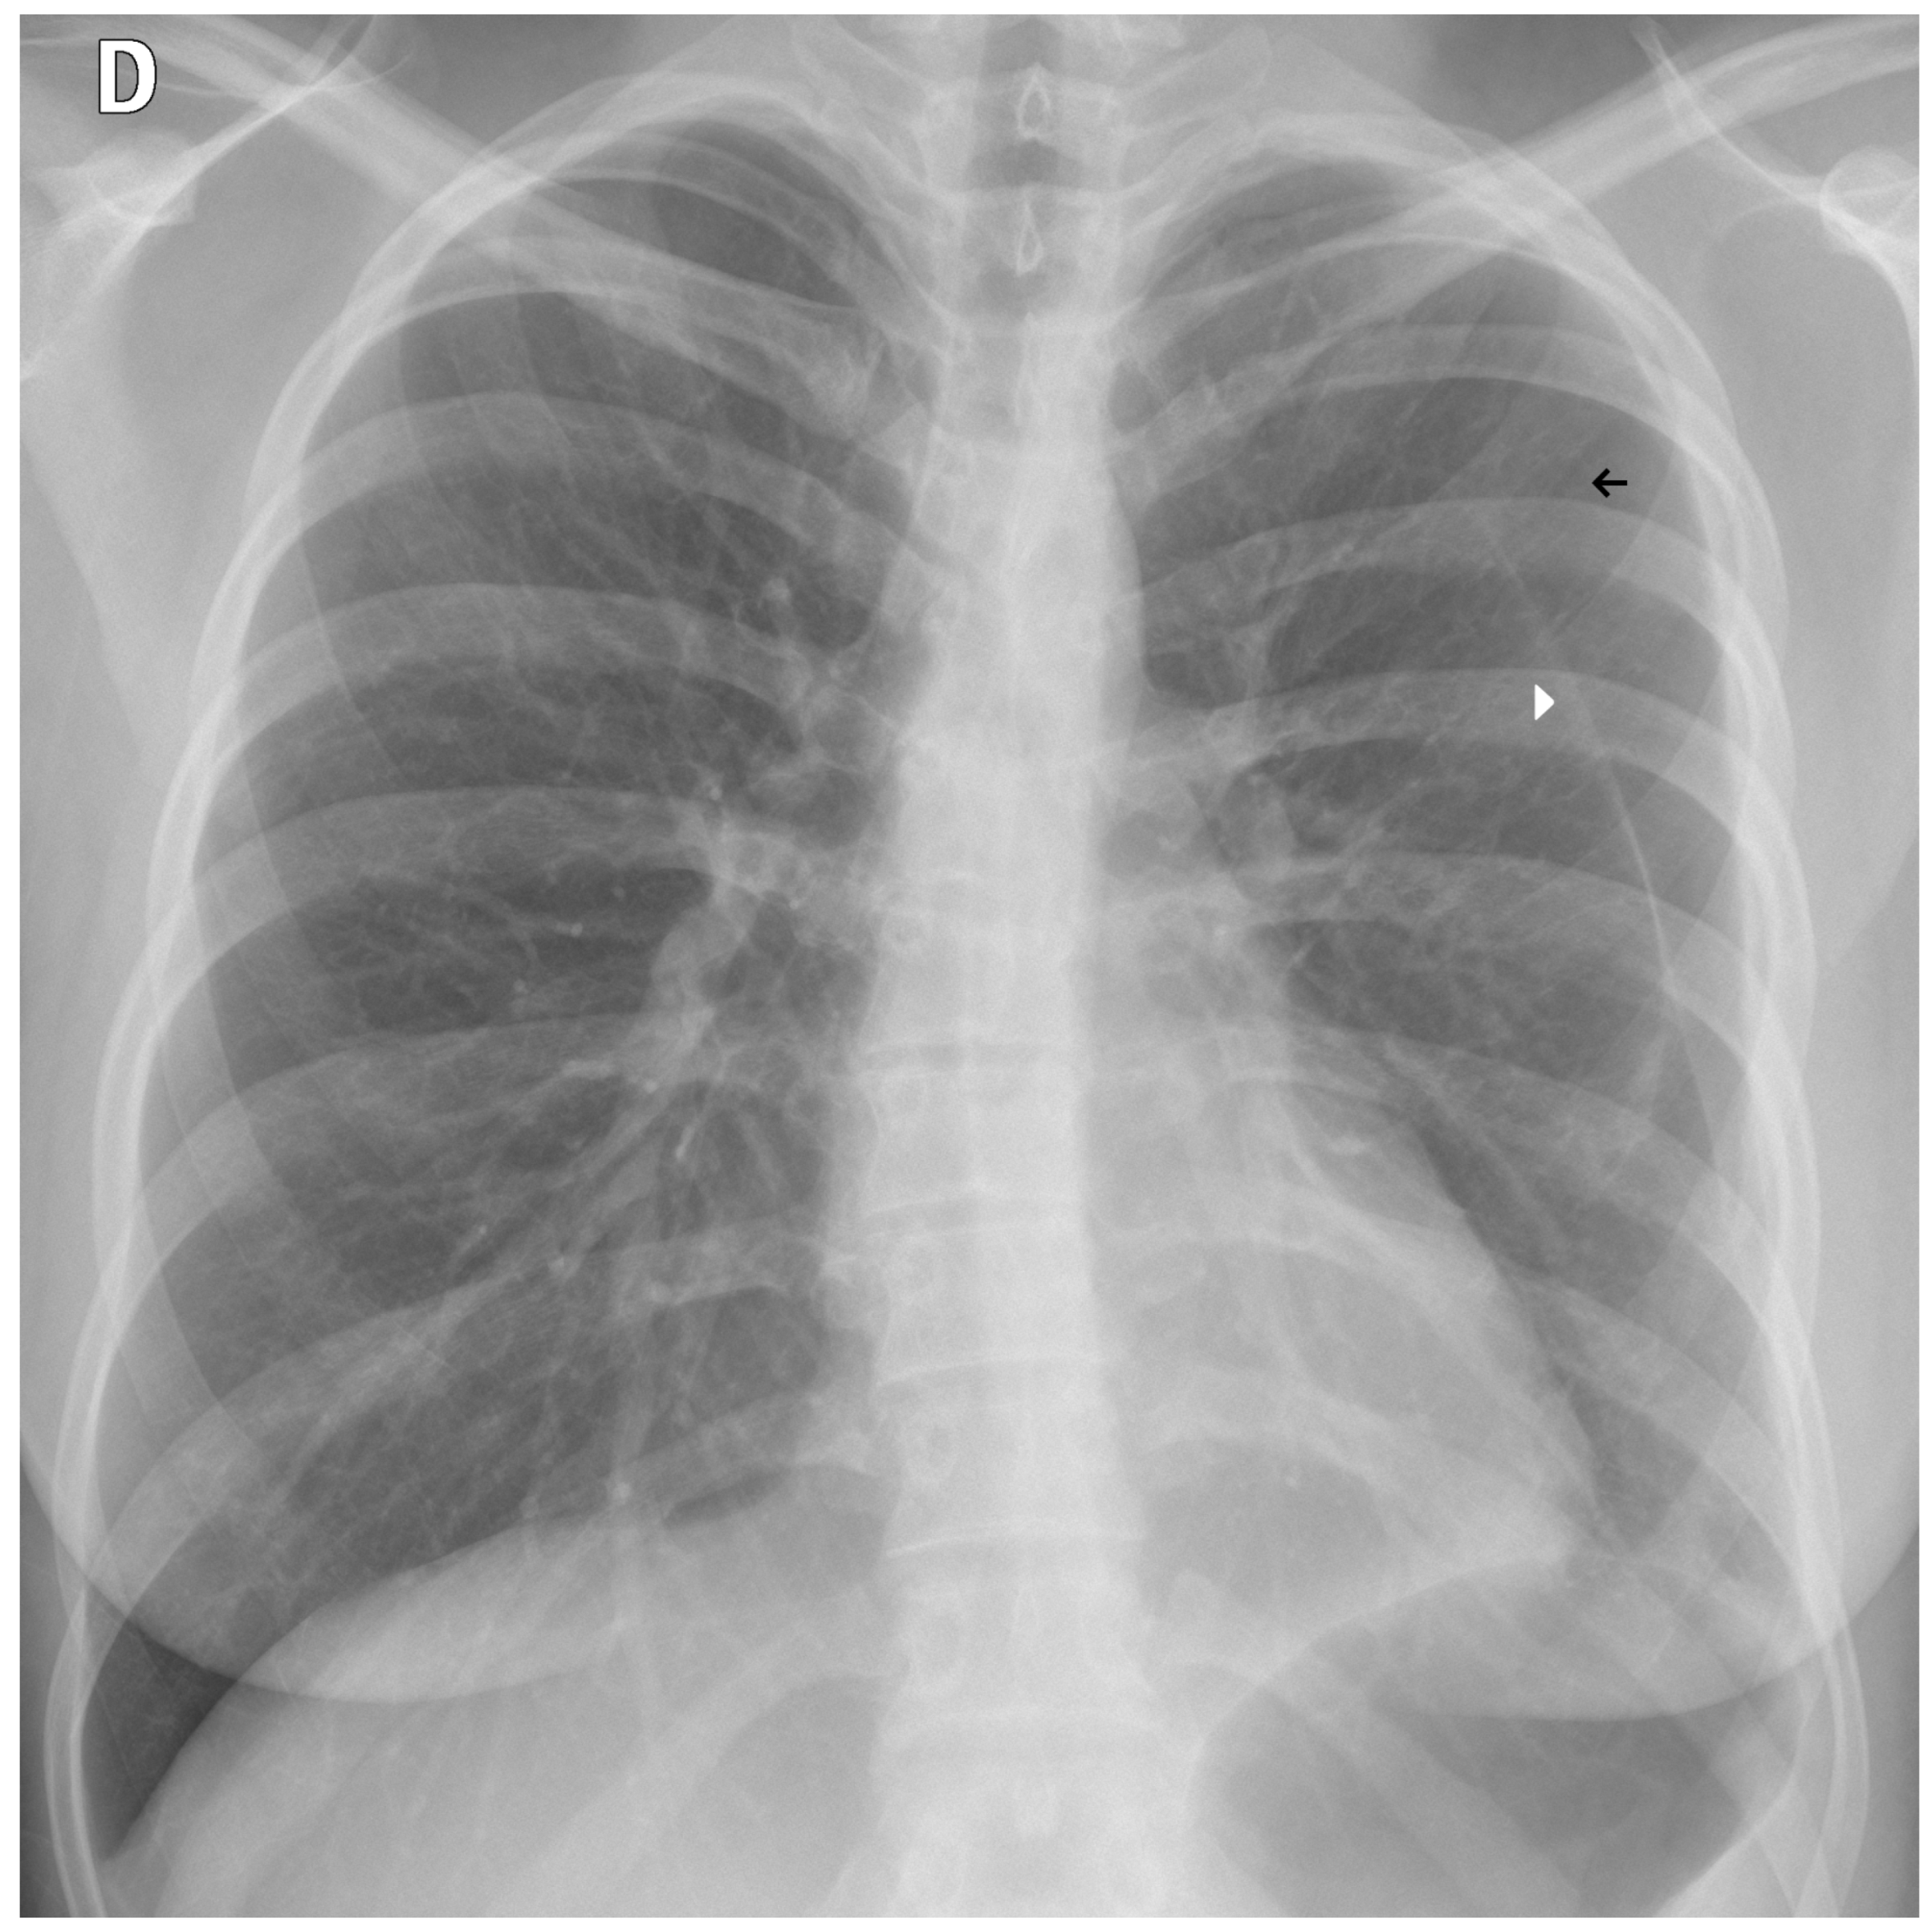

We employed a U-Net architecture with a MobileNetV2 backbone to segment the thoracic region and generate a unified “tongue-shaped” mask encompassing both lungs as well as the mediastinal and hilar regions. We chose U-Net for its proven effectiveness in medical image segmentation tasks, where high spatial precision is required. Its encoder–decoder “U” structure enabled the capture of both contextual and spatial information, facilitating the delineation of complex anatomical structures with high resolution. In this study, segmentation was used not only to isolate the relevant pulmonary region but also to constrain the subsequent classifier’s focus to clinically meaningful areas, thereby improving accuracy and reducing noise from irrelevant image regions.

We resized input images to 512 × 512 pixels and performed data augmentation using geometric and photometric transformations (padding, Gaussian noise, CLAHE, brightness/gamma adjustment, blur, motion blur, and hue/saturation shifts). The model was trained for 40 epochs with a batch size of 8 using the Adam optimizer (initial learning rate = 5 × 10−5) and a composite loss function combining Dice loss and binary focal loss to balance region overlap and class imbalance. Performance was monitored using Intersection over Union and F-score metrics, and the best model was selected by minimizing the validation loss with adaptive learning rate scheduling. Figure 2 illustrates the resulting mask, which ensures inclusion of central thoracic structures.

Figure 2. Example of first-stage segmentation: the generated “tongue-shaped” mask covering both lungs and mediastinal structures.